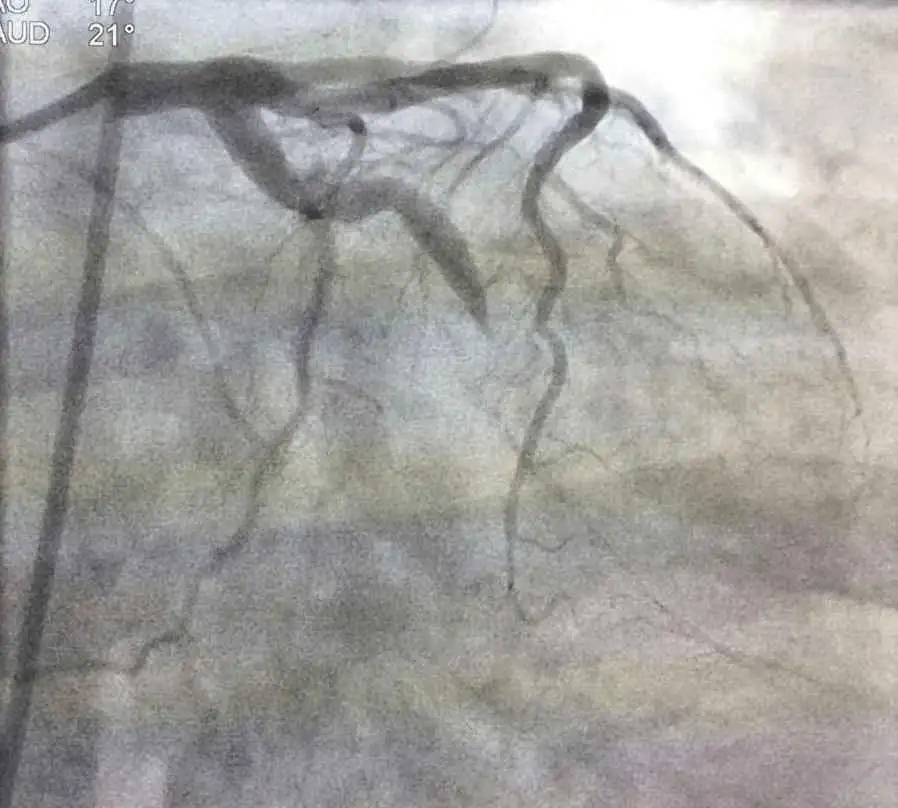

This is an RAO Caudal view of the left coronary system. It reveals a totally occluded left anterior descending artery (LAD) and left circumflex obtuse marginal branch. The LAD is a very large blood vessel that is responsible for blood flow to most of the anterior wall of the heart. This is a very large infarction. Without intervention, death is the likely outcome of this type of occlusion. As you can see below, the patient’s right coronary artery that is responsible for circulation to the inferior wall of the heart is patent and continues to supply blood flow to that portion of the heart muscle.

You can see from the above angiogram that blood flow has been restored to a large amount of heart muscle by opening the left anterior descending artery that was occluded when this gentleman came into the emergency department. He will be maintained on Plavix 75 mg daily. A nitroglycerin drip may be used to reduce the workload on his heart for a couple of days. In addition, he will be placed on a beta blocker to decrease the workload and decrease the chance of re-infarction in the future. An ACE Inhibitor and a Statin will probably be part of his discharge regimen.